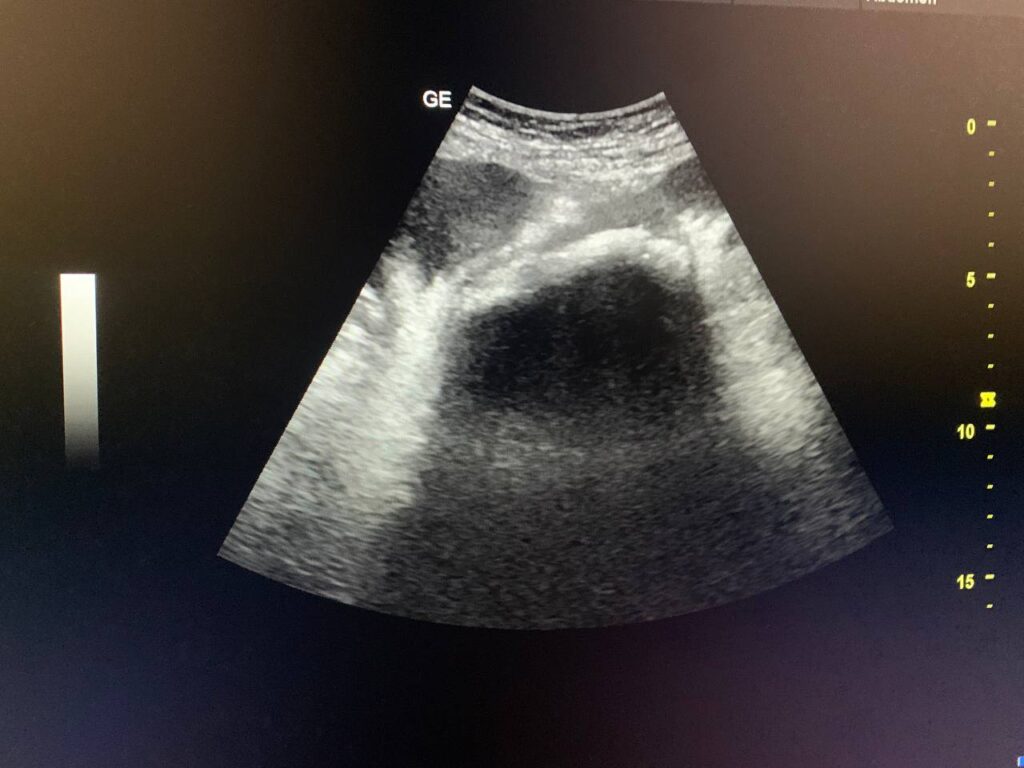

A para 3 woman with a history of 3 cesarean sections presented with abdominal pain. Ultrasound findings are as follows:

(Presence of left adnexal mass contain long irregular echogenic shadow with acoustic shadow behind , its size >80mm , could be (air shadow ) , abscess , or bowel mass , or foreign body , others ? )